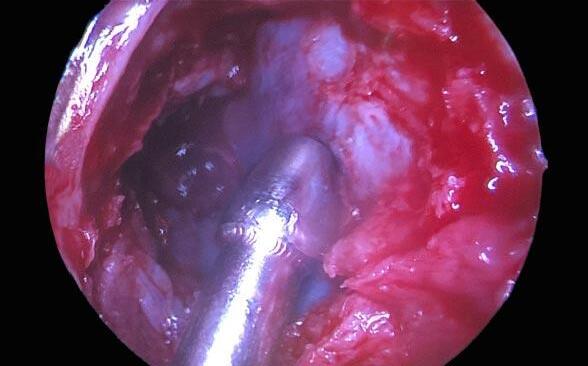

la proptosis y del dolor. Se solicita una tomografía computada (TC) de órbitas que evidencia marcada proptosis ocular izquierda (Imagen B1) asociada a alteración del plano graso intraconal a predominio inferior, impresionando aumento del grosor del músculo recto inferior izquierdo en probable relación a cambios edematosos inflamatorios ( Imagen B2 ). Se decide la realización de una descompresión orbitaria endoscópica de urgencia llevada a cabo por el equipo de otorrinolaringología. En el procedimiento se libera completamente la lámina pa-

pirácea del etmoides y se reseca la misma hasta evidenciarse la periorbita medial ( Imagen C ). Se procede a la apertura de la periorbita en forma longitudinal con la consiguiente herniación de grasa orbitaria y coágulos intraorbitarios. En el control postoperatorio, la paciente continúa con visión no luz, pupila midriática, sin evolución favorable pese a la intervención quirúrgica.

Imagen B2: TC de órbitas en corte coronal que evidencia alteración del plano graso intraconal a Imagen B1: TC de órbitas en corte axial que evidencia marcada proptosis izquierda. Imagen C: Fotografía de cámara de video de endoscopia endonasal que evidencia la apertura de la pared medial de la órbita, visualizando la periórbita medial.